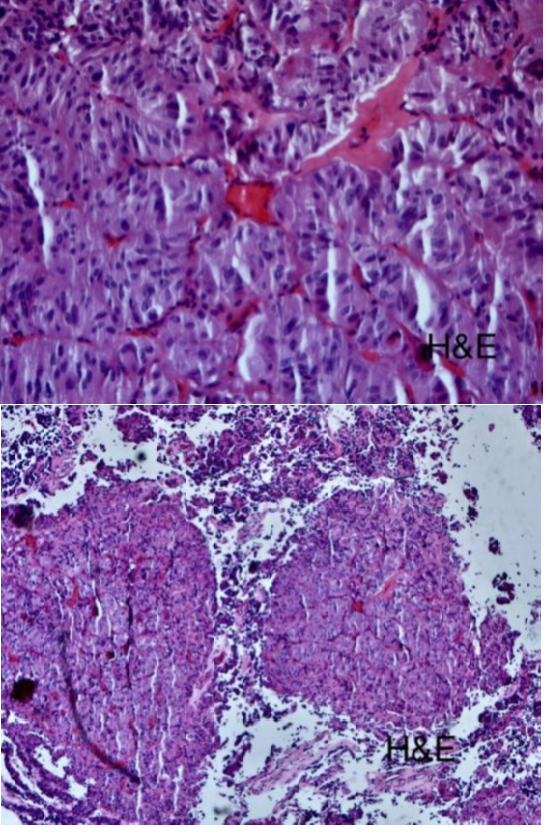

Histopathological staining proved the thyrotropinoma diagnosis (Figure 5) (Figure 6).9

Figure 4 Hematoxylin and eosin stain.